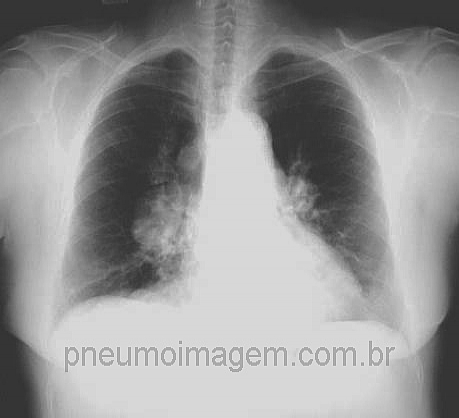

CASO CLÍNICO #63

Qual é o nome da doença que mais comumente leva a esse alargamento bilateral e simétrico do mediastino, com aspecto em saco de batatas? Deixe seus comentários abaixo.

What is the name of the disease that most commonly leads to this bilateral and symmetrical enlargement of the mediastinum? Write your comments below.